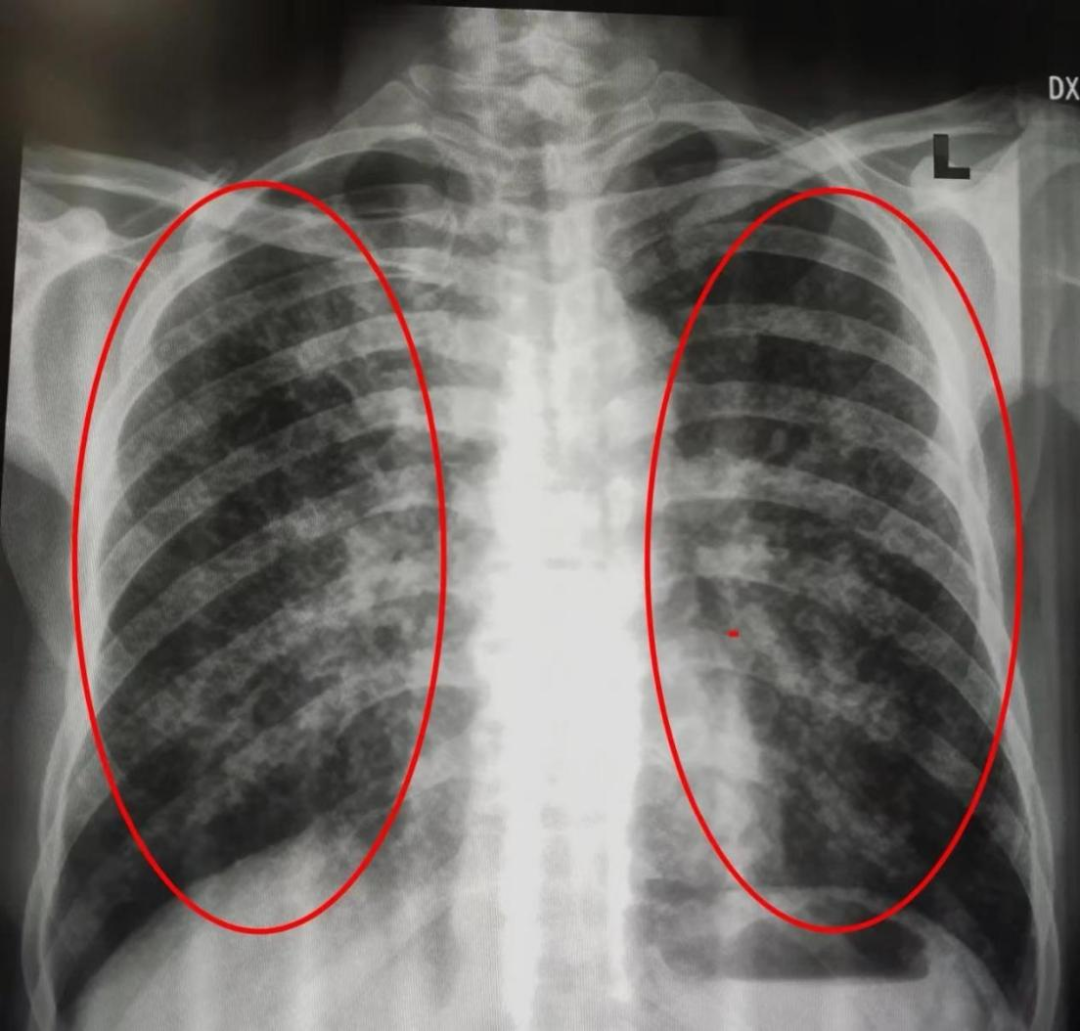

(胸部正常平片)

当X线透过人体后投射到采集板上所形成的黑白影像,是二维叠加的图像,所以肺部早期病变是有可能被肋骨、心影、胸壁软组织等重叠所干扰,肺部小结节也容易被隐藏,胸片一般只能查到15~20mm的肿瘤。在实际工作中,当胸片发现了肺部异常,需要做CT进一步排查,进一步确诊还要做 增强CT 。